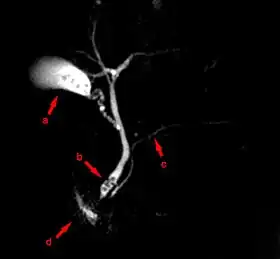

MRCP image showing stones in the distal common bile duct: (a) Gallbladder with stones, (b) Stones in bile duct, (c) Pancreatic duct, (d) Duodenum. | |

Magnetic resonance cholangiopancreatography (MRCP) is a medical imaging technique. It uses magnetic resonance imaging to visualize the biliary and pancreatic ducts non-invasively. This procedure can be used to determine whether gallstones are lodged in any of the ducts surrounding the gallbladder.

MRCP is used to diagnose gallstones. It can also diagnose choledochal cysts very reliably.[5] Besides providing information regarding the biliary system, MRCP also provides information regarding surrounding solid organs and blood vessels, thus useful for planning the resection of pancreatic cancer and look for complications of primary sclerosing cholangitis such as liver cirrhosis and cholangiocarcinoma.[5]